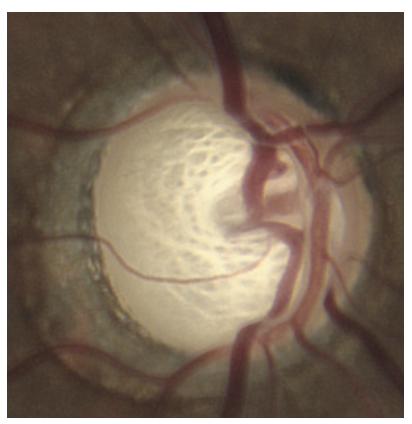

Degeneração Macular Relacionada a Idade (DMRI)

Oclusões Vasculares da retina